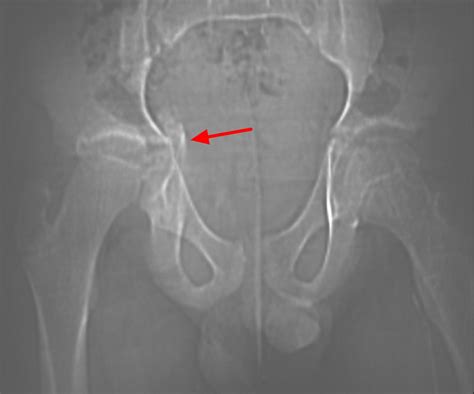

Identifying a Growth Plate Fracture early is critical for successful treatment. Common symptoms include persistent pain during movement, an inability to bear weight on the affected limb, and visible swelling or tenderness. In some cases, the limb may appear deformed or shortened. When you visit a healthcare professional, they will typically perform the following diagnostic steps:

• X-ray Imaging: The primary tool for diagnosis, though it is important to note that growth plates can be difficult to see on standard X-rays, often requiring comparisons to the uninjured limb.